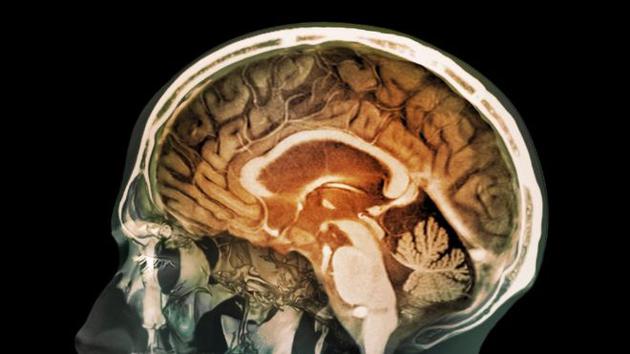

污染空氣毒性微粒可直接進(jìn)人類大腦 或誘發(fā)老年癡呆

最新研究顯示,人體大腦組織中存在微小的磁鐵微粒,這些微??赡苁强諝馕廴舅隆Q芯糠治霰砻?,大腦中存在大量磁鐵微粒,可能誘發(fā)阿爾茨海默癥和其他神經(jīng)退行性疾病。

新浪科技訊 北京時(shí)間11月29日消息,據(jù)國(guó)外媒體報(bào)道,空氣污染中的磁鐵微粒被懷疑具有毒性,吸入人體可直接進(jìn)入大腦,可能誘發(fā)老年癡呆癥等疾病。

目前這項(xiàng)最新研究首次證實(shí)具有污染性的磁鐵微粒能夠進(jìn)入人類大腦,2016年初,世界衛(wèi)生組織警告稱,空氣污染每年導(dǎo)致300多萬(wàn)人過(guò)早死亡。